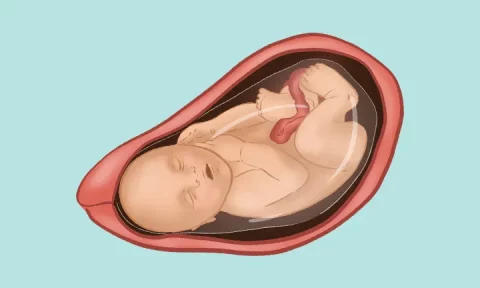

در طول دوران بارداری، توجه به رشد و تکامل جنین بسیار مهم است. از آزمایشهای ضروری مانند غربالگریها گرفته تا معاینات ماهانه، همه برای بررسی سلامت جنین انجام میشوند. همچنین، مطالعه درباره رشد و تربیت کودک و آمادگی برای یک تا ۱۲ ماهگی نوزاد، میتواند به والدین کمک کند تا برای این مرحله از زندگی آمادهتر باشند.